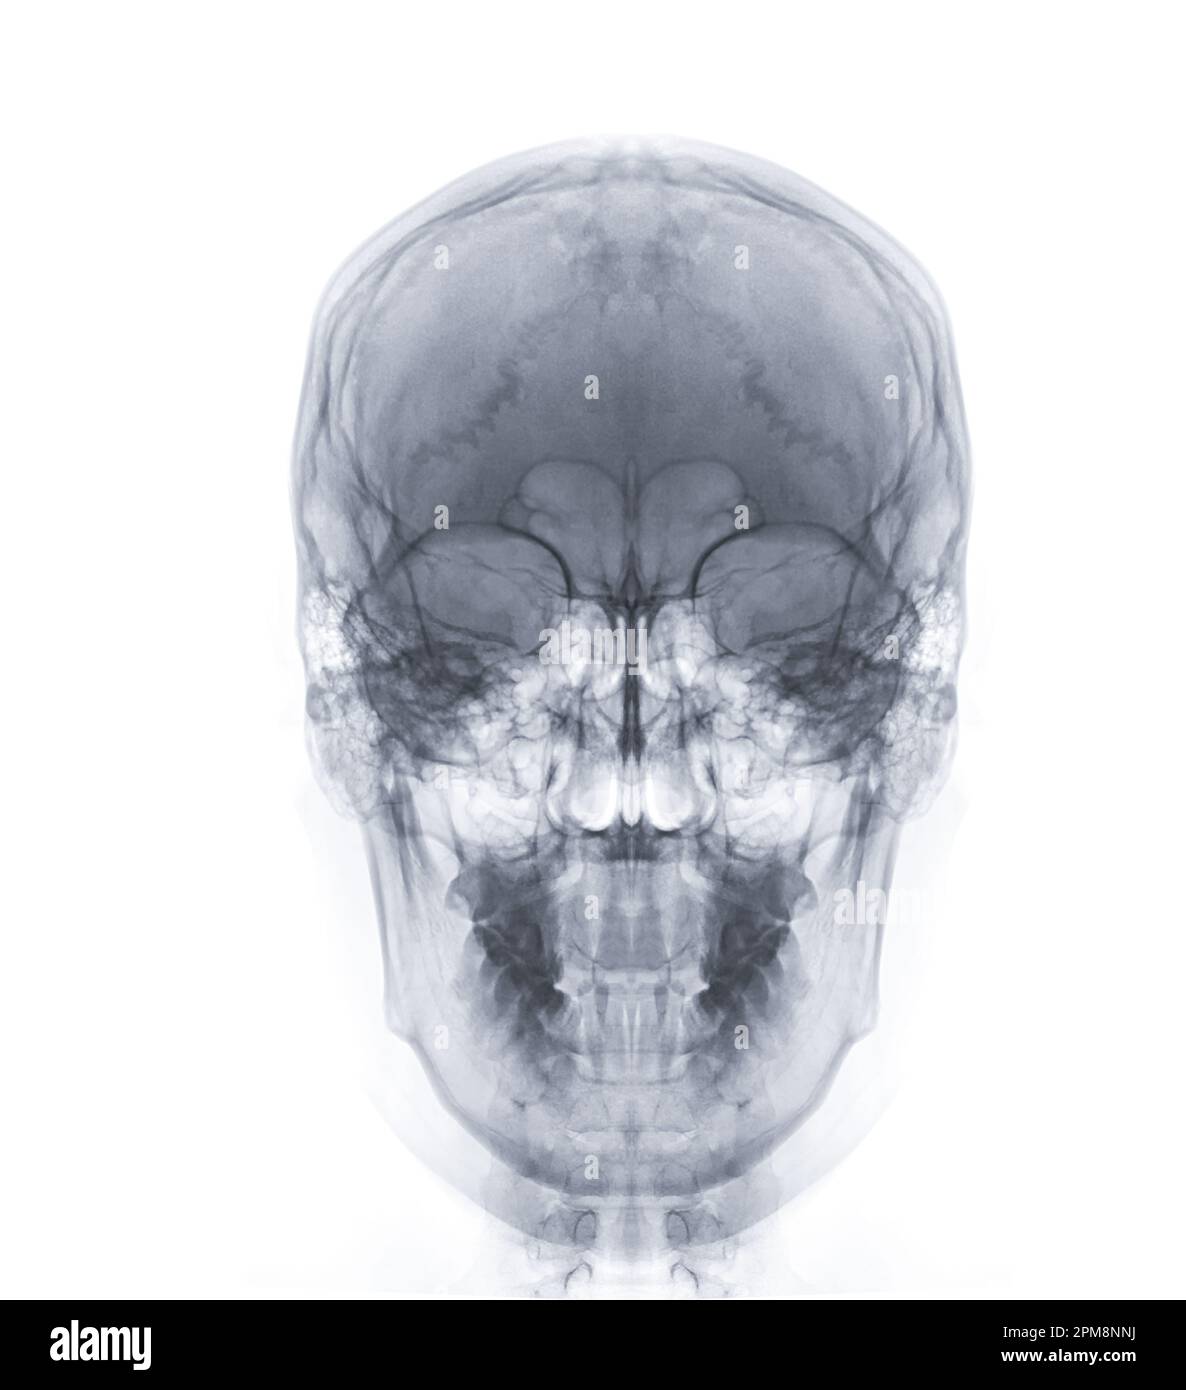

Prepare to be captivated by List, a showcase of real human skull front view black and white imagery powered by ieltschampions.edu.vn. More related visuals are below.

real human skull front view black and white

Posts: real human skull front view black and white